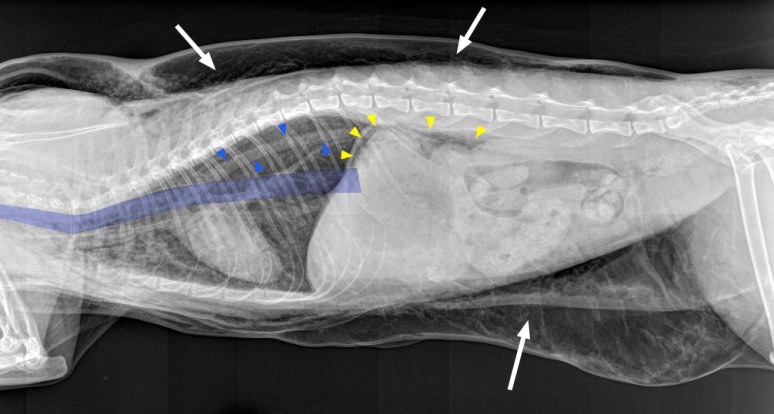

On note tout d’abord une quantité marquée de gaz qui dissèque les plans adipeux sous-cutanés (flèches blanches), donnant cette apparence de vagues ondulantes à la périphérie de notre chat. Dans la cavité thoracique, on remarque que les structures médiastinales sont soulignées, notamment les contours de l’aorte (flèches bleues), les parois externes de la trachée, l’oesophage thoracique (en bleu) de même que certains gros vaisseaux (tronc brachio-céphalique, veine cave craniale) autrement invisibles. Cette apparence indique la présence d’un pneumomédiastin. On note également que la silhouette cardiaque est légèrement décollée du sternum et que le diaphragme apparaît aplati. Même si un pneumomédiastin peut évoluer en pneumothorax, ce n’était pas le cas ici (voir plus loin l’explication de ces signes). On note enfin du gaz dans l’espace rétro-péritonéal et autour de la partie dorsale de l’estomac (flèches jaunes).

Tout comme la majorité d’entre vous, avec la présence d’un emphysème sous-cutané, d’un pneumomédiastin et d’un pneumopéritoine aussi importants, nous avons tout de suite suspecté une lésion aux voies respiratoires supérieures pendant la procédure de dentisterie, soit à l’intubation (stylet), pendant l’anesthésie (ballonet surgonflé) ou à l’extubation (retrait du tube endotrachéal alors que le ballonet est toujours gonflé). Et comme le traitement de ce genre de cas est la plupart du temps conservateur, l’air sous-cutané a été drainé et le patient mis sous observation. Toutefois, le chat a continué de se détériorer dans les heures suivantes, à tel point qu’il a été placé dans la cage à oxygène. Des radiographies du cou ont alors été réalisées afin de chercher une explication pour cette détérioration.